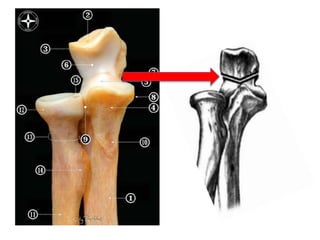

Proximal

Ulna

Diaphyseal

Angle